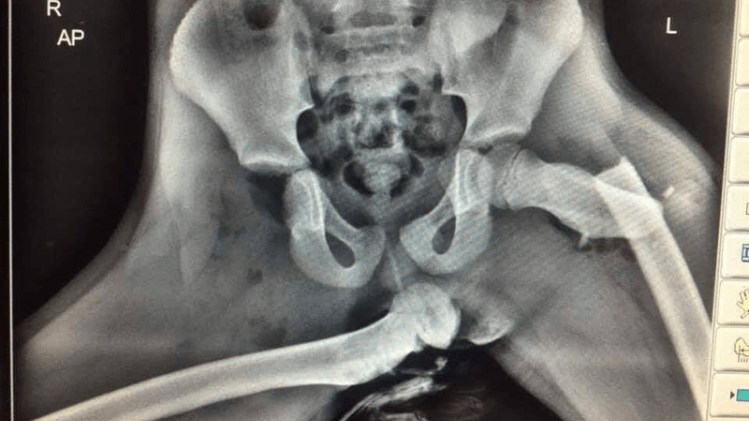

En 2020, la police galloise avait diffusé une radiographie sur laquelle on pouvait voir la hanche d’une dame être totalement disloquée, alors que l’autre est tout simplement brisée. Des blessures graves survenues parce qu’elle avait posé, en tant que passagère, ses jambes sur le tableau de bord au moment où la voiture dans laquelle elle se trouvait a eu un accident. «Si vous voyez votre passager avec les pieds sur le tableau de bord, arrêtez de conduire et montrez-lui ceci», expliquait l’officier. L’émission «MythBusters» avait déjà sensibilisé aux dangers de cette pratique. S’ils avaient conclu qu’elle n’était pas mortelle, les conséquences en cas d’accident peuvent être extrêmement graves. Un airbag se gonflant en moyenne entre 200 et 300 km/h.